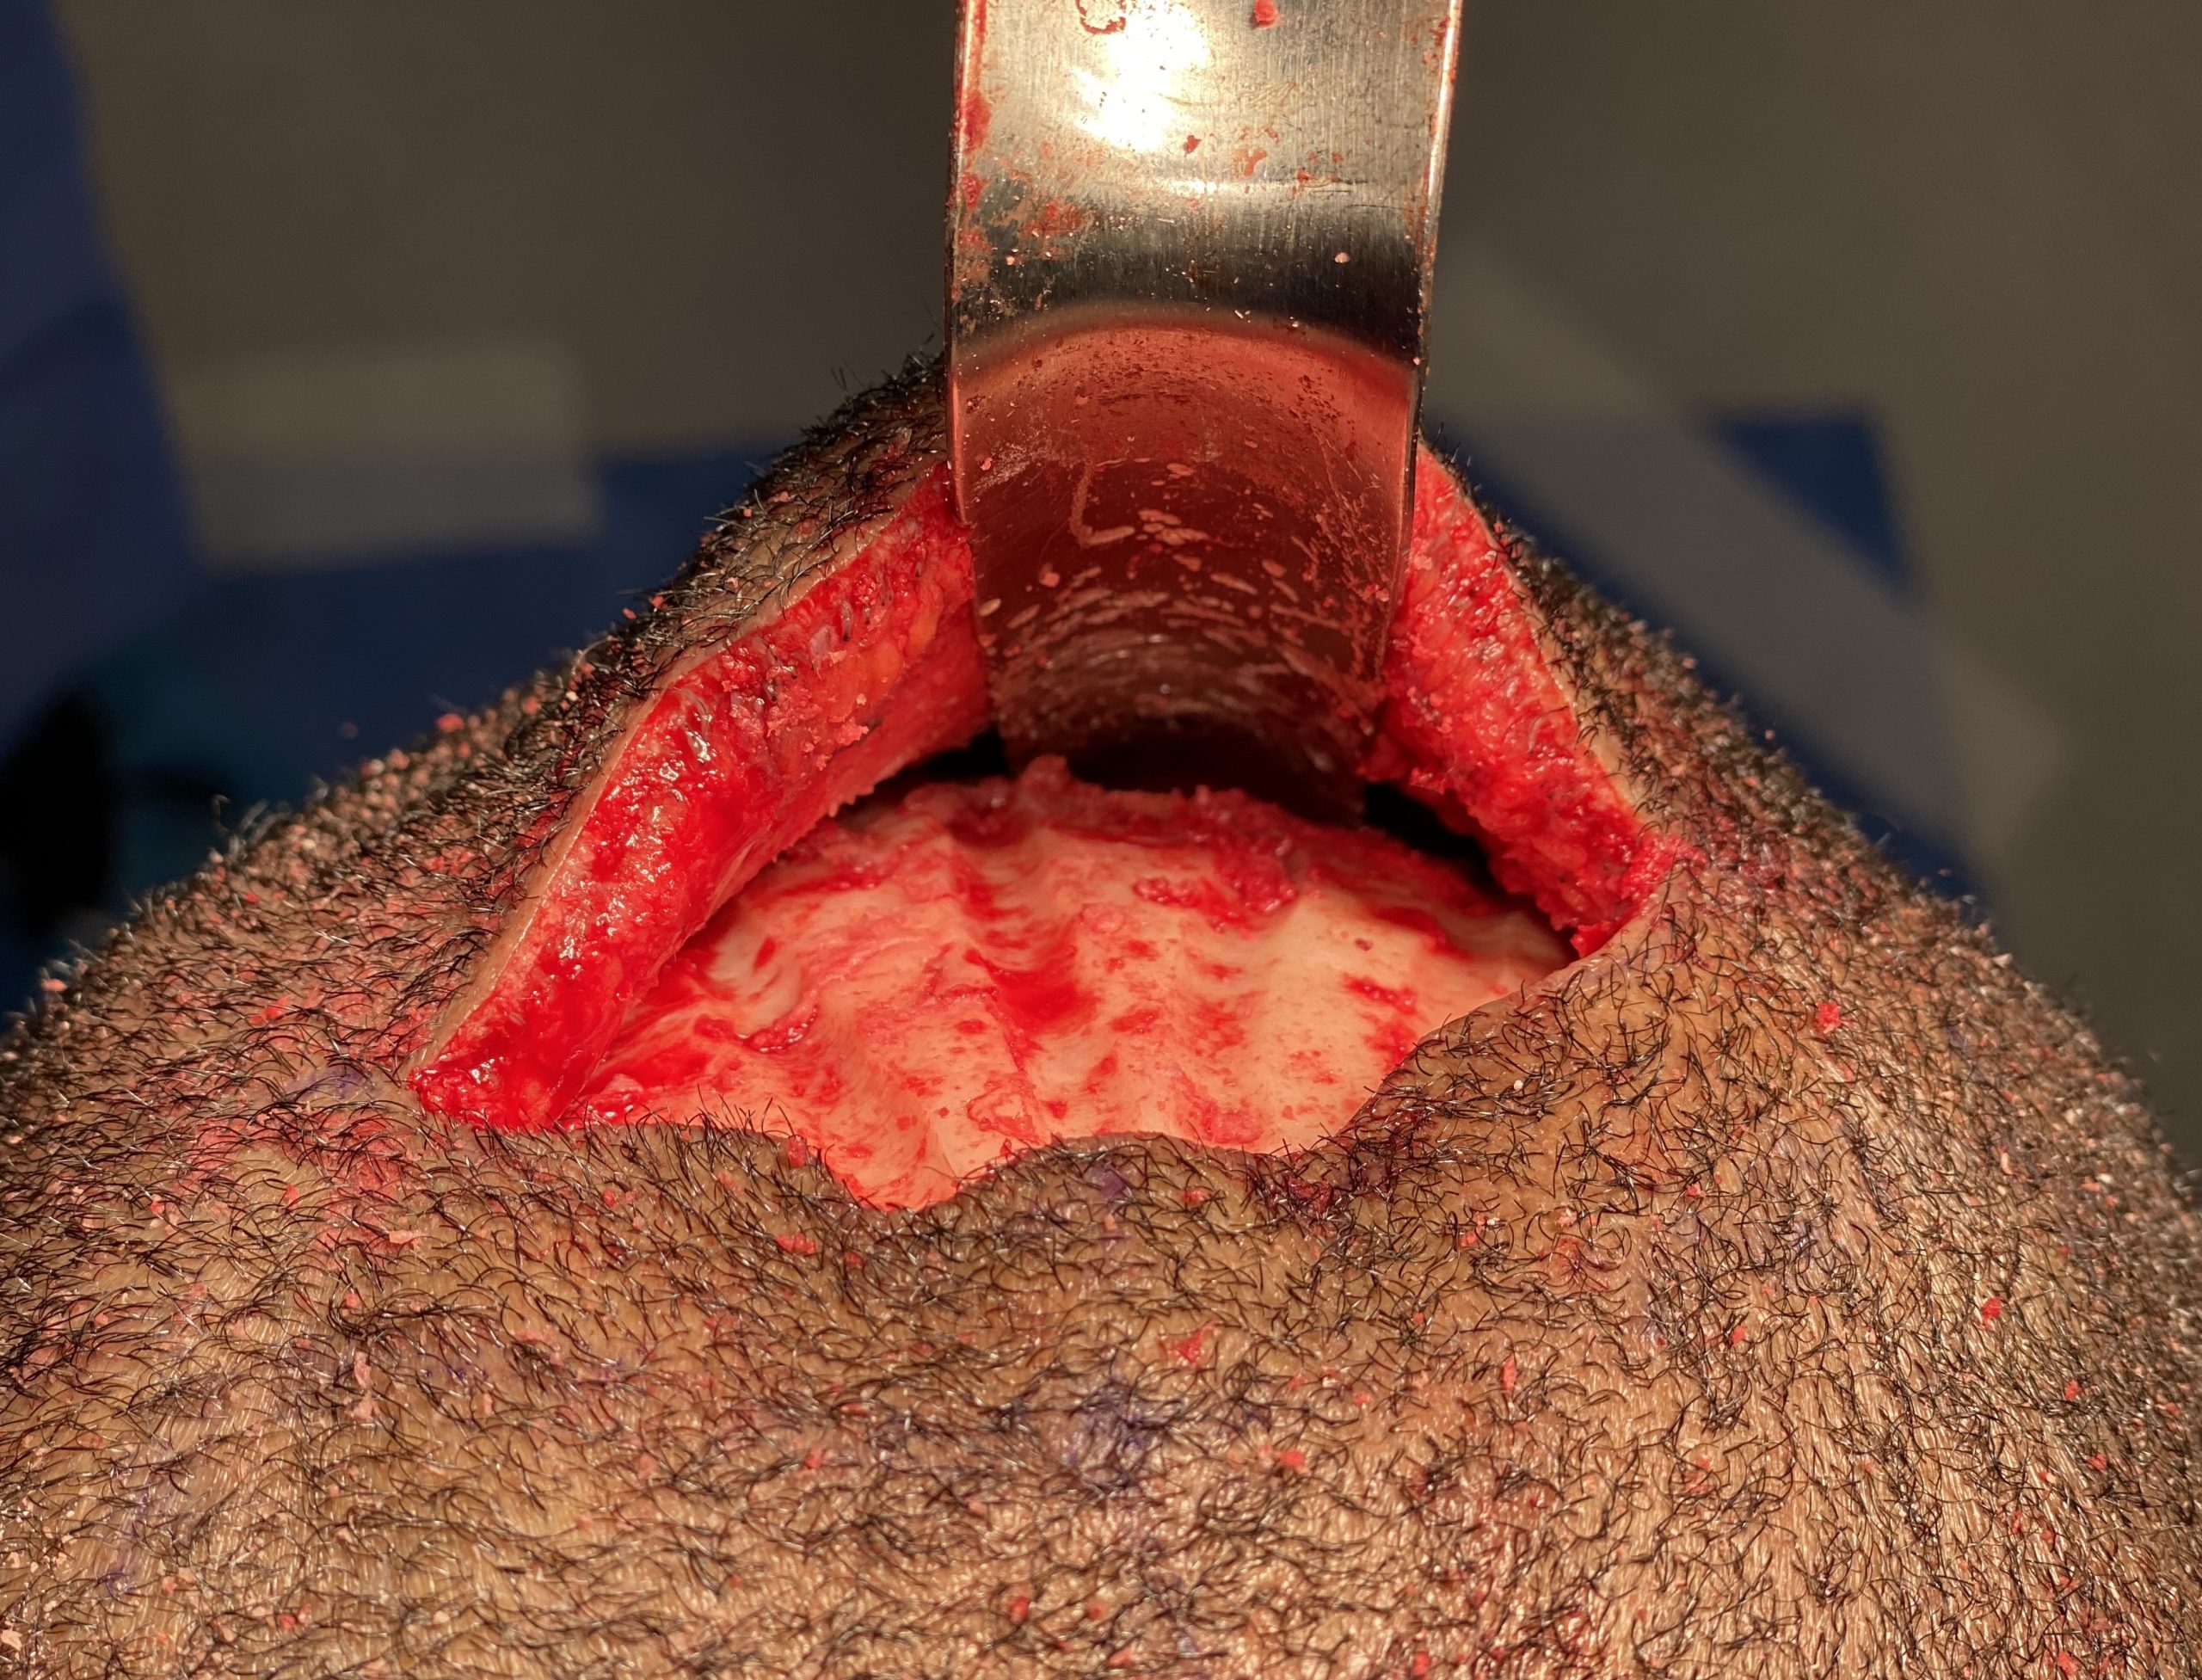

Desire for reduction of prominent occipital knob deformity.

Intraoperative result from occipital knob skull reduction through a direct small scalp incision.

Desire for reduction of prominent occipital knob deformity.

Intraoperative result from occipital knob skull reduction through a direct small scalp incision.